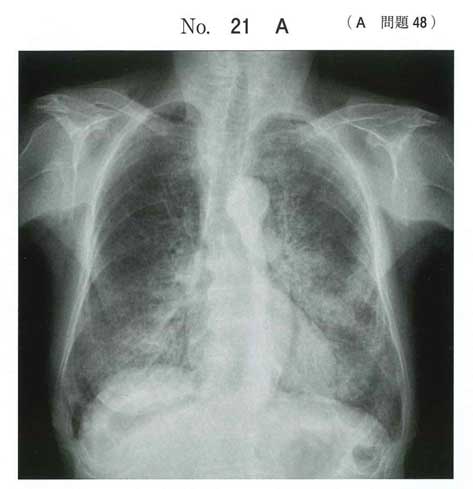

a:メロン皮状の網目陰影が特徴的

サーファクタントの貯留によって、すりガラス様陰影が地図上にみられ、しばしばメロン皮状に網目陰影(crazy-paving appearance)を呈する.